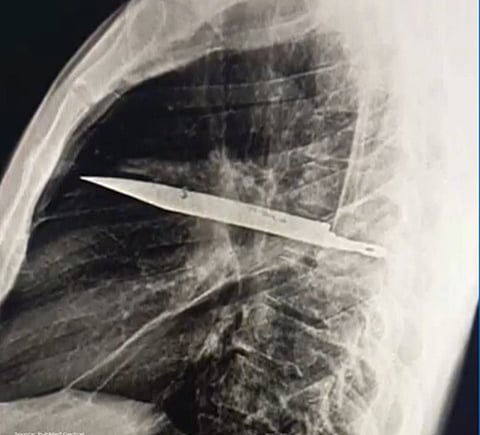

After visiting the general team at Muhimbili National Hospital, the patient received comprehensive treatment for the old stab wound. Initial imaging revealed that the knife blade had entered through his right shoulder area and remained embedded in his chest all these years.